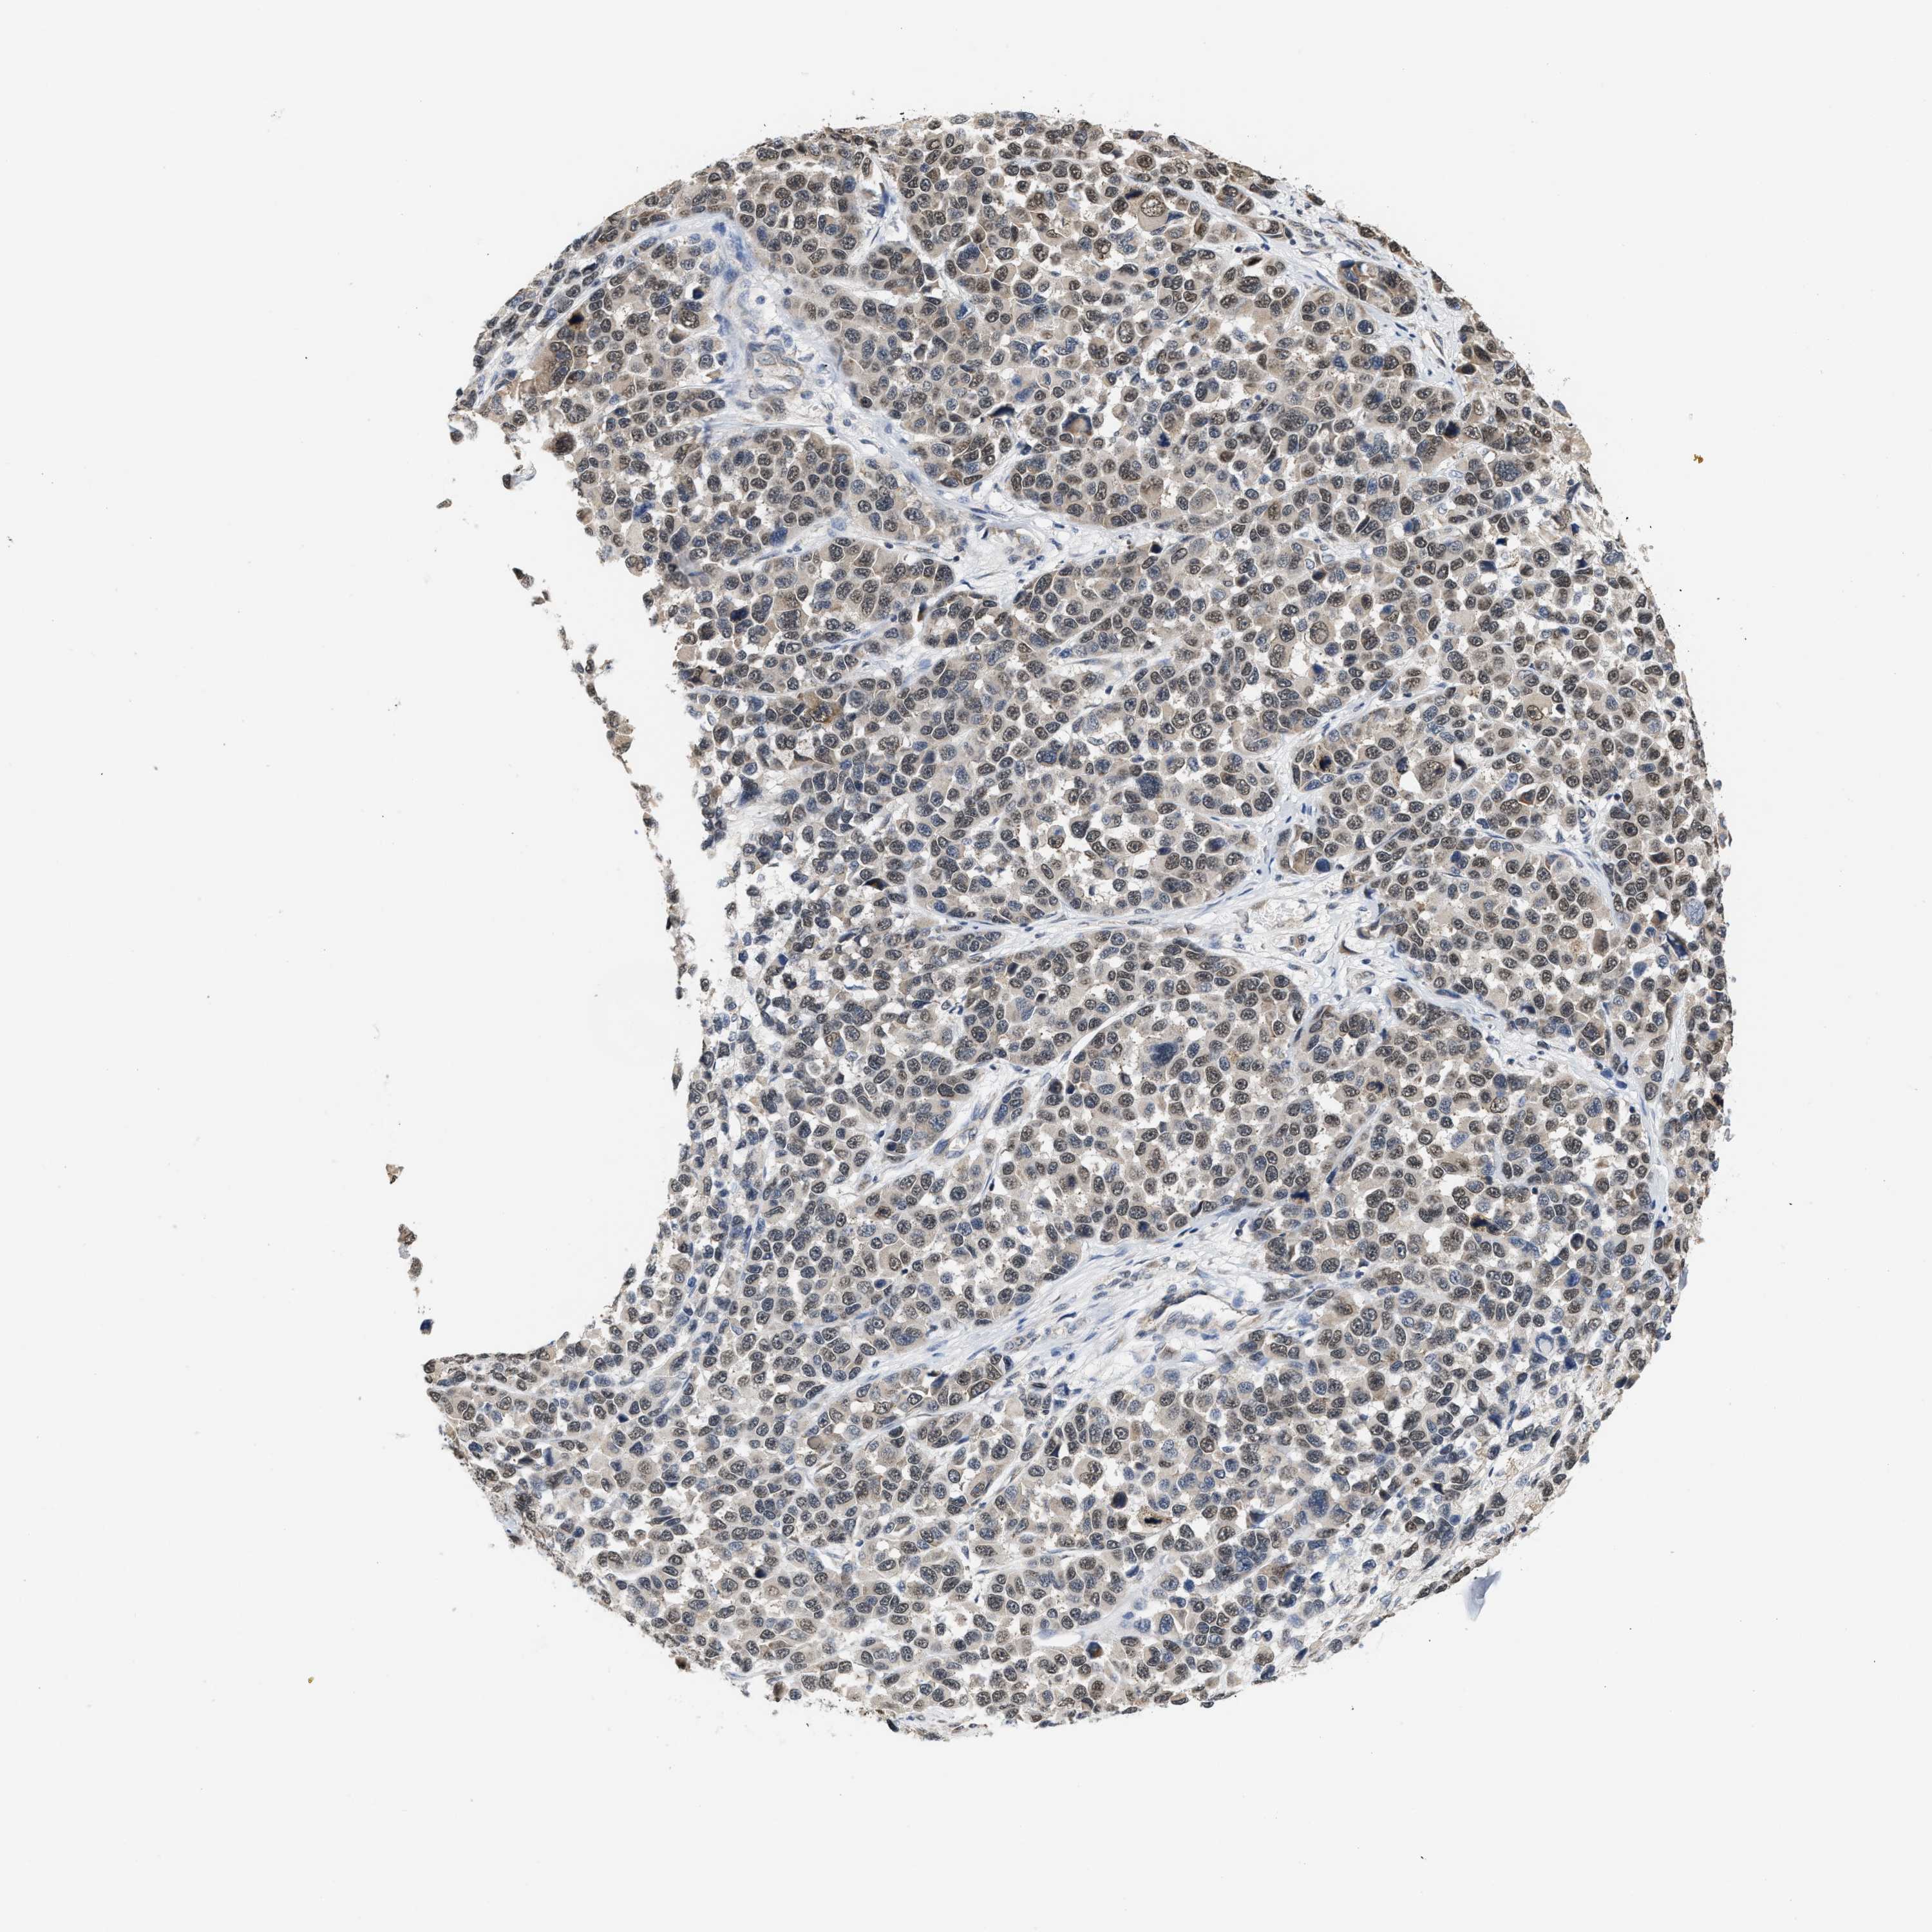

MELANOMA - Protein expressioni

A mouse-over function shows sample information and annotation data. Click on an image to view it in a full screen mode. Samples can be filtered based on level of antibody staining by selecting one or several of the following categories: high, medium, low and not detected. The assay and annotation is described here.

Note that samples used for immunohistochemistry by the Human Protein Atlas do not correspond to samples in the TCGA dataset.

Antibody stainingi

Antibody staining in the annotated cell types in the current human tissue is reported as not detected, low, medium, or high, based on conventional immunohistochemistry profiling in selected tissues. This score is based on the combination of the staining intensity and fraction of stained cells.

Each image is clickable and will lead to virtual microscopy that enables deeper exploration of all samples and also displays staining intensity scores, fraction scores and subcellular localization as well as patient and tissue information for each sample.

Antibody HPA020999

Antibody HPA023995

Staining

High

Medium

Low

Not detected

Intensity

Strong

Moderate

Weak

Negative

Quantity

>75%

75%-25%

<25%

None

Location

Nuclear

Cytoplasmic/membranous

Cytoplasmic/membranous,nuclear

Malignant melanoma, NOS

Malignant melanoma, Metastatic site